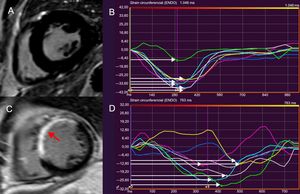

ETIOLOGÍAS DE LA MUERTE SÚBITA CARDIACA: SUSTRATOS ARRITMÓGENOS Y EVIDENCIA DE LA ESTRATIFICACIÓN DEL RIESGO CON LA RMCEnfermedad coronariaLa enfermedad coronaria es la causa más habitual de MSC, debida a la arritmogenicidad de la cicatriz posterior al infarto7. Las pruebas que vinculan la presencia y la carga del RTG a la AV/MSC en el contexto crónico posterior al infarto proceden de varios estudios (tabla 1, figura 1)7,25-30. En 195 pacientes con enfermedad coronaria sospechada sometidos a RMC, la presencia de RTG se relacionó de manera independiente con el desenlace clínico, incluidas las AV que requerían la descarga apropiada del DAI (hazard ratio [HR]=5,98; intervalo de confianza del 95% [IC95%], 2,68-13,3; p <0,0001)30. La carga del RTG (calculada como masa cicatricial) se relacionó de manera independiente con el tratamiento apropiado del DAI en 66 pacientes con enfermedad coronaria crónica (HR=3,15; IC95%, 1,35-7,33; p <0,001)25. El RTG también se relaciona con AV y MSC en el contexto posterior al infarto agudo31,32. En una cohorte de pacientes con enfermedad coronaria, se vio que la proporción entre la zona alrededor del infarto y la zona central (como medida de la zona gris: cicatriz densa) se relacionaba de modo independiente con la AV sostenida y el tratamiento apropiado del DAI (HR=2,01; IC95%, 1,17-3,44; p=0,01)28. En pacientes que han sufrido infarto, las anomalías del strain circunferencial (en las secuencias de tagging) se relacionan con AV inducible y caracterizan la zona gris alrededor del infarto18-20. La dispersión mecánica del VI se relacionó independientemente con la mortalidad y la MSC, incluida la AV y el tratamiento apropiado del DAI (HR=1,39; IC95%, 1,20-1,62; p <0,001) en una cohorte de 130 pacientes que habían sufrido infarto de miocardio con elevación del segmento ST (figura 1)23.

Resonancia magnética cardiaca de rastreo de características para evaluar la DMVI. La DMVI se define como la desviación estándar del tiempo hasta alcanzar el strain circunferencial máximo, expresada como porcentaje de la longitud del ciclo cardiaco. La imagen A muestra el corte medioventricular de eje corto del VI de un sujeto sano, en el que se observa ausencia de RTG. Se constata que la DMVI del paciente es normal (A) por medio de la deformación sincronizada de los distintos segmentos del VI (señalados con distintos colores) y del tiempo hasta alcanzar el nivel máximo de strain circunferencial, indicado con flechas blancas (B). La imagen C muestra el adelgazamiento y la extensión del RTG en el septo interventricular y la pared anterior del VI tras sufrir un infarto de miocardio (flecha). Aumento de la DMVI (11,8%) en el paciente (C), que refleja la disincronía en los segmentos del VI (D). La DMVI> 9,79% se relaciona con arritmias ventriculares y riesgo de muerte súbita cardiaca tras sufrir un infarto. DMVI: dispersión mecánica del ventrículo izquierdo; RTG: realce tardío de gadolinio; VI: ventrículo izquierdo. Esta figura se muestra a todo color solo en la versión electrónica del artículo.